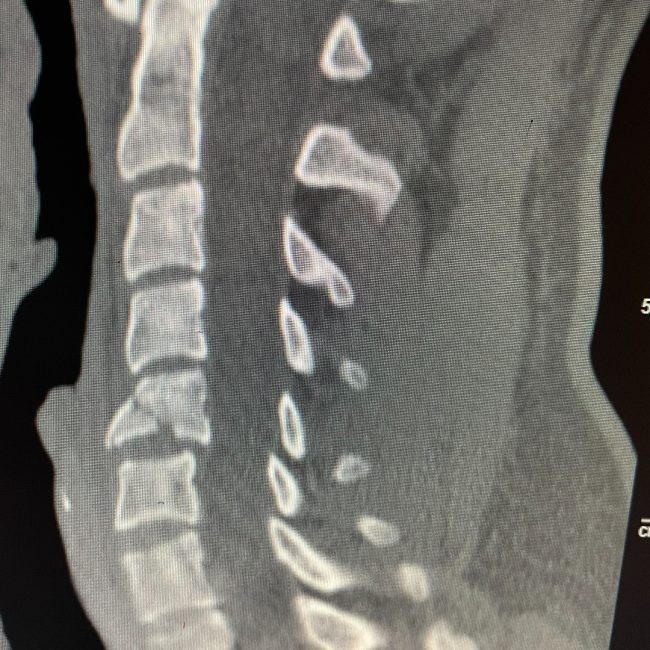

Combined Anterior–Posterior Repair Restores Function After C5 Diving Fracture

As a Neurosurgeon, spinal fractures of the neck from diving accidents are things that I see way too often. This young man dove from a boat into shallow water. He presented with some numbness in his arm and hand. He had a fracture with the instability of his cervical spine at C5, requiring anterior and…